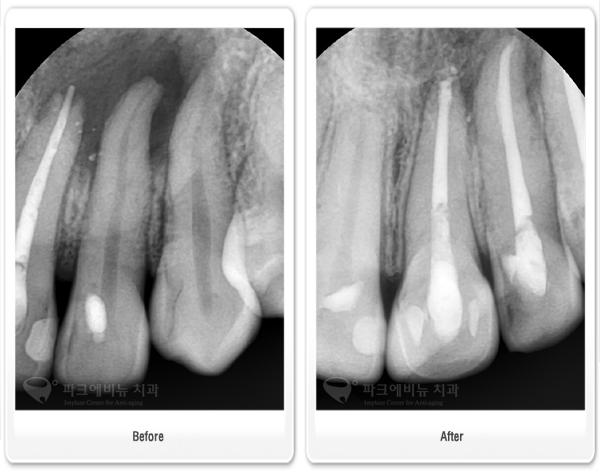

파크에비뉴치과 충치 수면마취, 수면신경치료 전 후 비교

#21,22,23- 첫 내원 했을 당시, 왼쪽 위 대문이 옆 치아 뿌리 끝에 염증이 생겼던 것이 점점 옆으로 퍼지면서 큰 낭종을 형성하고 있었다. 수 차례에 걸쳐서 신경치료를 시행 한 결과 염증이 제거 되면서 자연적으로 낭종이 있던 부위에 치조골이 차오르며 상태가 호전되어 신경치료를 마무리 할 수 있었다.